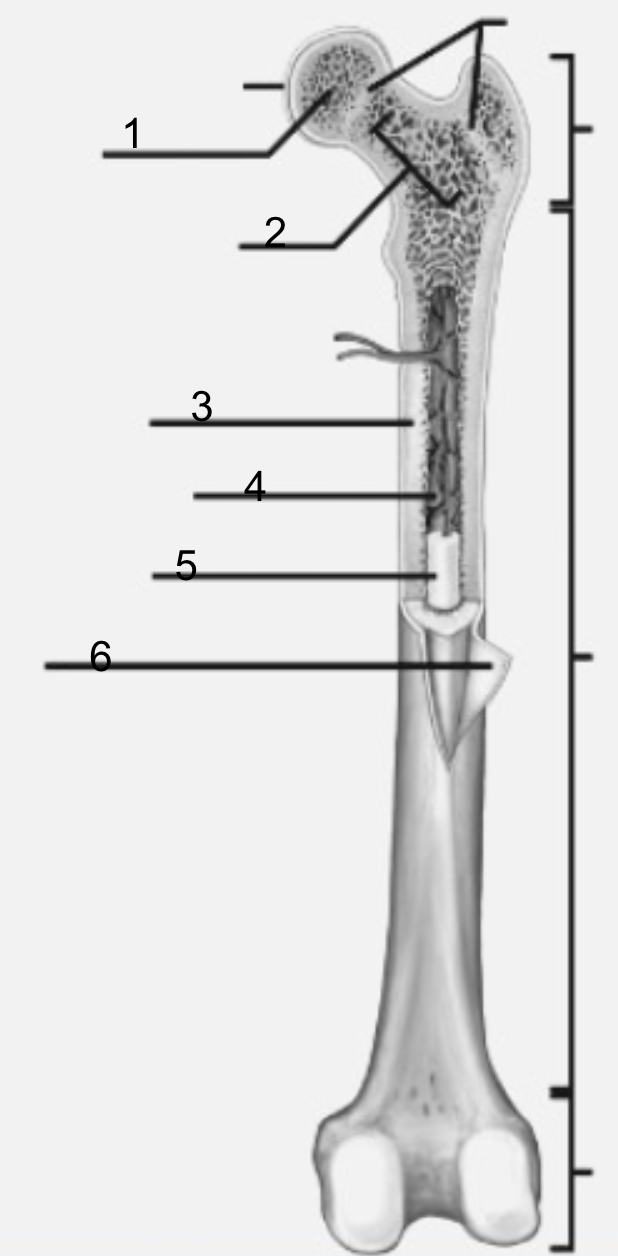

what is 1

epiphysis

what is 2

spongy bone

what is 3

periosteum

what is 4

diaphysis

osteclast

dissolves and breaks down old or damaged bone cells

what is 5

epiphyseal plate (line)

what is 6

yellow bone marrow

what is 1

Epiphysis

functions of Epiphysis

For articulations (when two or more bone meet and join )

what is 3

diaphysis

function of diaphysis

the transport of oxygen and immune support, and mineral and fat storage.

where is medullary cavity housed

diaphysis

what is the medullary cavity

hollow part of bone that contains bone marrow. The bone marrow makes blood cells and stores fat

where is the yellow marrow loacted?

medullary cavity

what is 2

metaphysis

functions of metaphysis

transfer loads from weight-bearing joint surfaces to the diaphysis